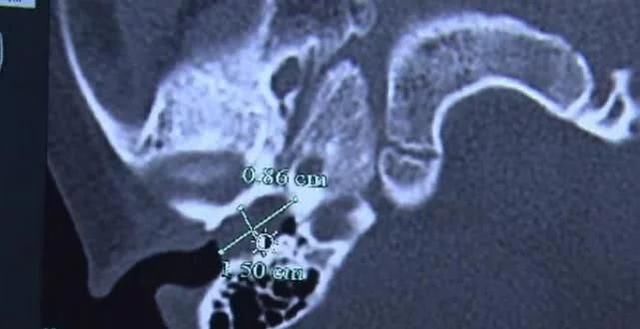

赵赵,一个5岁的男孩,几周前患了感冒引起的中耳炎。医生通过CT发现,孩子的耳道有一个很大的尾蚴阻塞,从外耳道一直阻塞到耳鼓。质地很硬,赵赵母亲说,孩子很活泼,所以自从孩子出生后,他们就再也没有掏出耳朵。出乎意料的是,这条拖船成了定时炸弹。

要取出这块耵聍并不是一件容易的事情,小孩子配合度低,用来溶化的药水也不管用,最后,医生只能通过对孩子进行全麻手术,取出了孩子耳中的耵聍,共计花费了5000元左右,那么,小朋友的耵聍应该怎么处理呢?